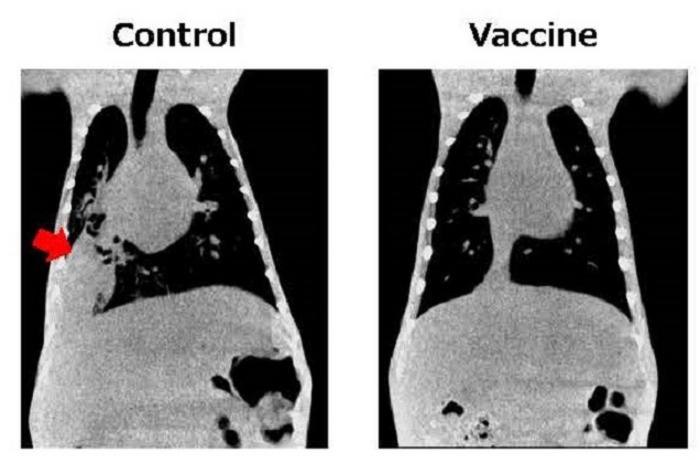

To successfully develop a novel pneumococcal vaccine, the research team combined its proprietary mucosal vaccine technology with pneumococcal surface proteins that can cover a wide range of serotypes. Experiments conducted on mice and macaques have demonstrated the vaccine’s efficacy in suppressing pneumococcal pneumonia in the target animal groups.